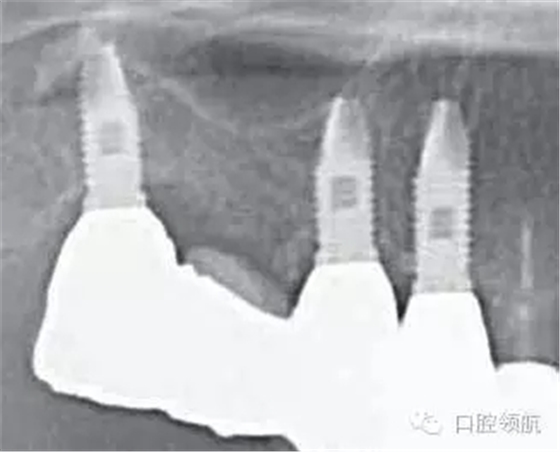

患者因?yàn)椋ㄗ笊系?顆牙) 種植體周?chē)つげ贿m為主訴來(lái)院。(圖1),2年前接受種植治療,每4個(gè)月檢查復(fù)診,但近幾周因身體的不適沒(méi)能堅(jiān)持做好清潔,臨床探診有出血,X線檢查后,沒(méi)有發(fā)現(xiàn)骨吸收現(xiàn)象(圖2)。

圖2 來(lái)院就診時(shí)的X線片,沒(méi)有發(fā)現(xiàn)骨吸收現(xiàn)象。